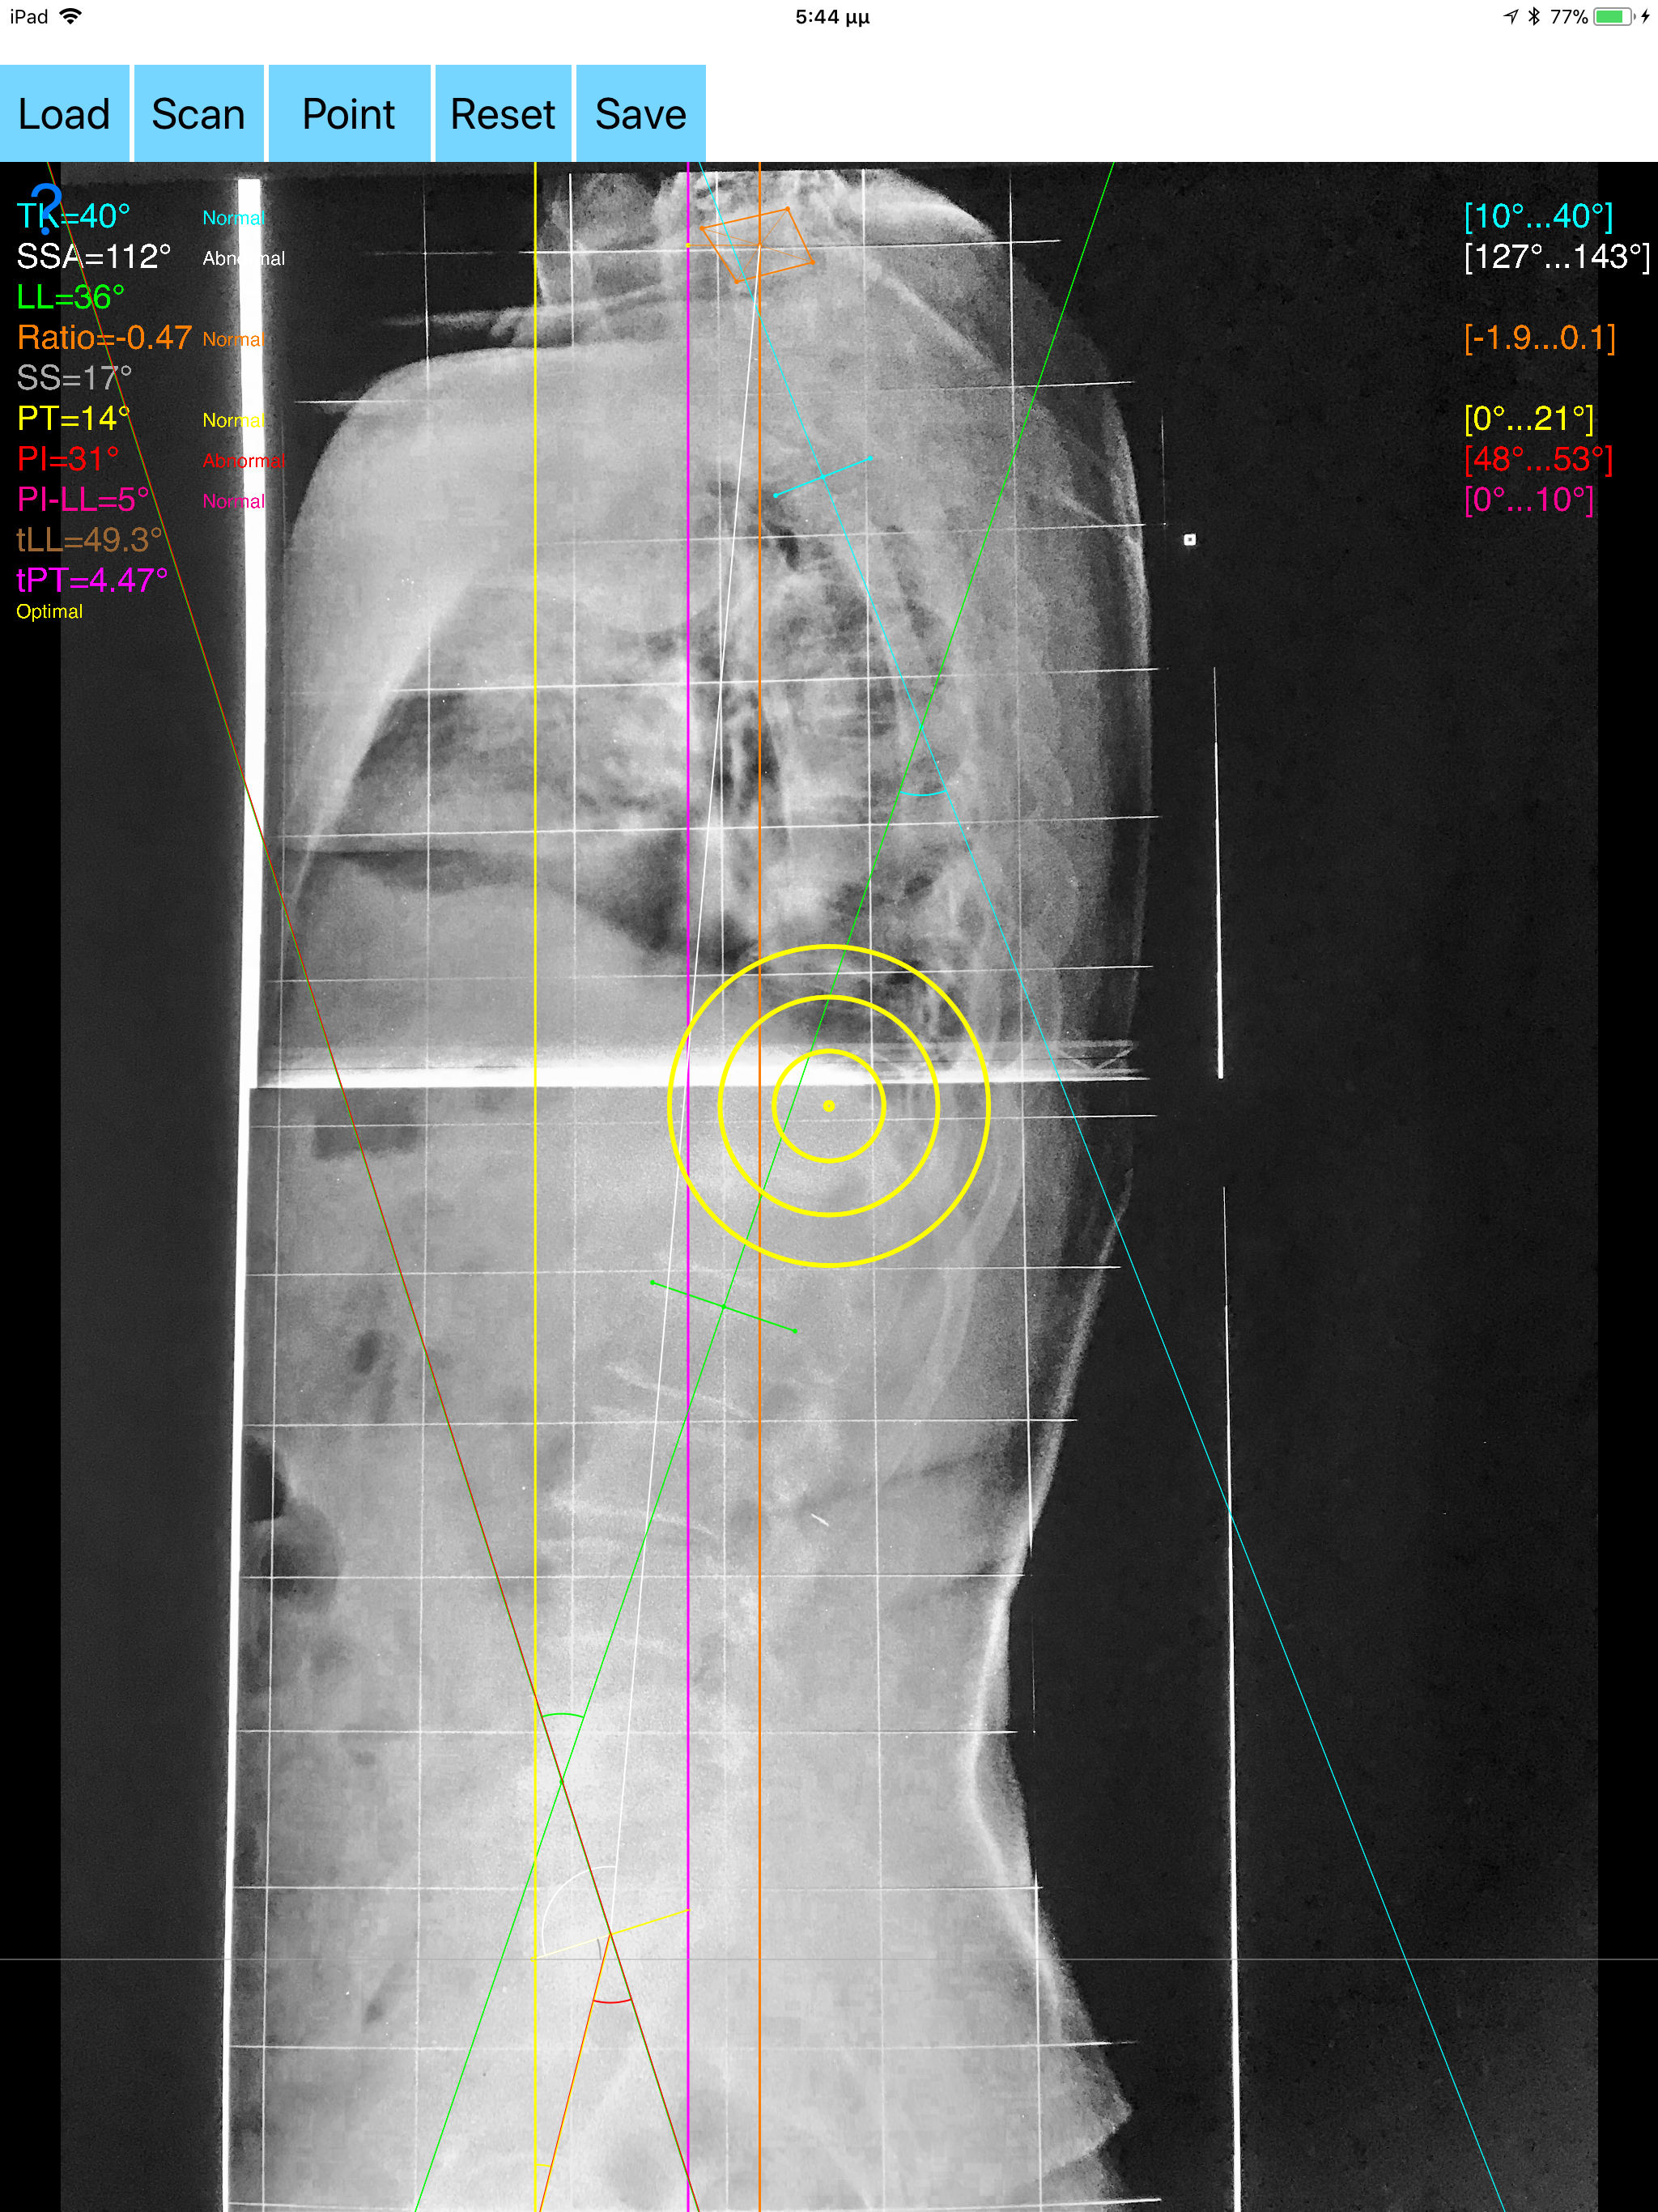

The assessment of global sagittal alignment and the compensatory mechanisms which are implicated in the spine and the spinopelvic jucture are of paramount importance for spine and joint replacement surgeon. The dynamic interplay between flexibility and balance around the axis of gravity determine the type and the amount of influence in spine and hips. Radiographic parameters to evaluate objectively the sagittal balance are Pelvic incidence (PI), Sacral slope (SS), Pelvic Tilt (PT), Lumbar lordosis (LL),Thoracic Kyphosis, C7 plumb line (C7PL) and its ratio. Drawings in patients X-rays and precise measurements are important in order to quantify the magnitude of spinal deformities, to monitor the success or failure of treatment and thus optimise the management of patients according to the severity of the imbalance. The Sagittal Balance App is medical software aimed for orthopaedic surgeons, providing tools that allow doctors to: -Securely import medical images directly from the camera or stored photos. -By marking several points at the image of X-ray, the App calculates and offers a very convenient way to determine the most accurate possibly way at once, Pelvic incidence (PI), Sacral slope (SS), Pelvic Tilt (PT), Lumbar lordosis (LL), thoracic kyphosis, C7 plumb line (C7PL), C7PLD/sfd ratio, PI–LL, theoretical normal pelvic tilt (tPT),theoretical normal L1-S1 lumbar lordosis (tL1S1), Spino-sacral angle (SSA) According to measured parameters the app categorizes the severity of the imbalance of spine, in three different stages: optimal balanced, balanced with compensatory mechanisms and imbalanced. -Save the planned images, for later review or consultation.The measured values are compared by normal reference databases and also data are exported as txt file, ready to print or to input as cells to excel for research. -The app also allows the calculations of centroids after choosing points in vertebra body in independent manner from order. All information received from the software output must be clinically reviewed regarding its plausibility before patient treatment! Sagittal Balance App indicated for assisting healthcare professionals. Clinical judgment and experience are required to properly use the software. The software is not for primary image interpretation. In a busy everyday practice, the examiner have to draw lines in X-rays or in clinical settings, this it is time consuming and cumbersome. Accessory instruments like protractors, hinged goniometers, well sharped pencils, rulers or even transparent papers must be available. The app offers a very convenient and accurate way to perform most common radiographic measurements for spine, and spinopelvic juncture in a blink of an eye in front of your screen. The build in feature of the app, allows results to be categorized may help decide what could be considered normal or pathologic. The app is not a simple goniometer, is an enhanced product which helps to monitor objectively the course of the treatment and evaluate optimally the spine. This App is particular useful especially in clinical settings where you need a quick results without losing time. Please see tutorial videos at the developer’s web site www.orthopractis.com Reference databases 1.Legaye J, Duval-Beaupe`re G, Hecquet J, Marty C (1998) Pelvic incidence: a fundamental pelvic parameter for three-dimensional regulation of spinal sagittal curves. Eur Spine J 7(2):99–103 2. Cavanilles-Walker JM, Ballestero C, Iborra M, Ubierna MT, Tomasi SO (2014). "Adult Spinal Deformity: Sagittal Imbalance". International Journal of Orthopaedics.